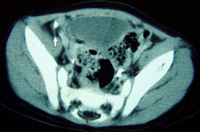

Tomografia computadorizada (TC) revelando abscesso intra-abdominal consistente com apêndice perfurado